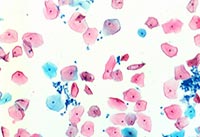

液基切片顯微圖片。 (操作提示:點(diǎn)擊圖片或使用鍵盤上的方向鍵來轉(zhuǎn)換要查看的圖片)